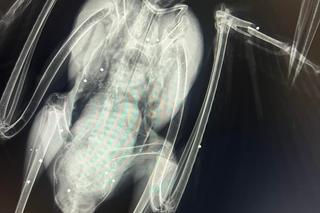

Na Podkarpaciu ktoś strzela do bocianów jak do żywych tarcz. W ostatnich dniach do Fundacji Ada w Przemyślu trafiło kilkanaście ptaków z ranami postrzałowymi. Jednego nie udało się uratować, był postrzelony aż 12 razy! Śrut zniszczył jego wątrobę, płuco, skrzydło i miednicę. Postrzelony bocian zazwyczaj kończy jako kaleki ptak, który już do końca życia nie będzie mógł żyć na wolności. Wszystkiemu winien jest człowiek.

Ostatnio fundacja zajmowała się trzema bocianami. Jednego z nich nie udało się uratować. Został postrzelony 12 razy.

- Ktoś sobie z tego bociana po prostu zrobił żywą tarczę. Miał w ciele mnóstwo śrutów, mnóstwo złamań. Niektóre były w okolicach płuc, serca - zaznacza lekarz weterynarii Angelika Szkolnik.

Obecnie pod skrzydła Fundacji trafiło kilka bocianów, każdy z ranami postrzałowymi. Każdy bezmyślnie skrzywdzony przez człowieka. Większość z nich jest w takim stanie, że już nigdy nie wzbije się w powietrze Na zawsze zostaną w bocianim szpitalu, który stworzyła Fundacja Ada. Ten znajduje się we Fredropolu nieopodal Przemyśla. Co roku trafia około 80 rannych ptaków. 60% z nich to bociany, a większość bocianów to niestety ofiary śrutu.